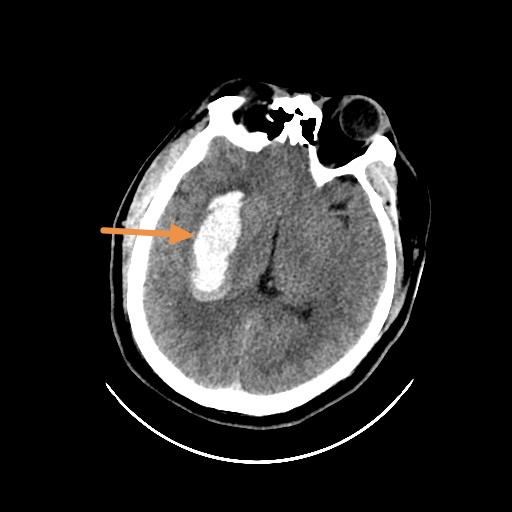

图1:非对比头颅ct显示双侧基底节(包括尾状核头,壳核,苍白球)对称性